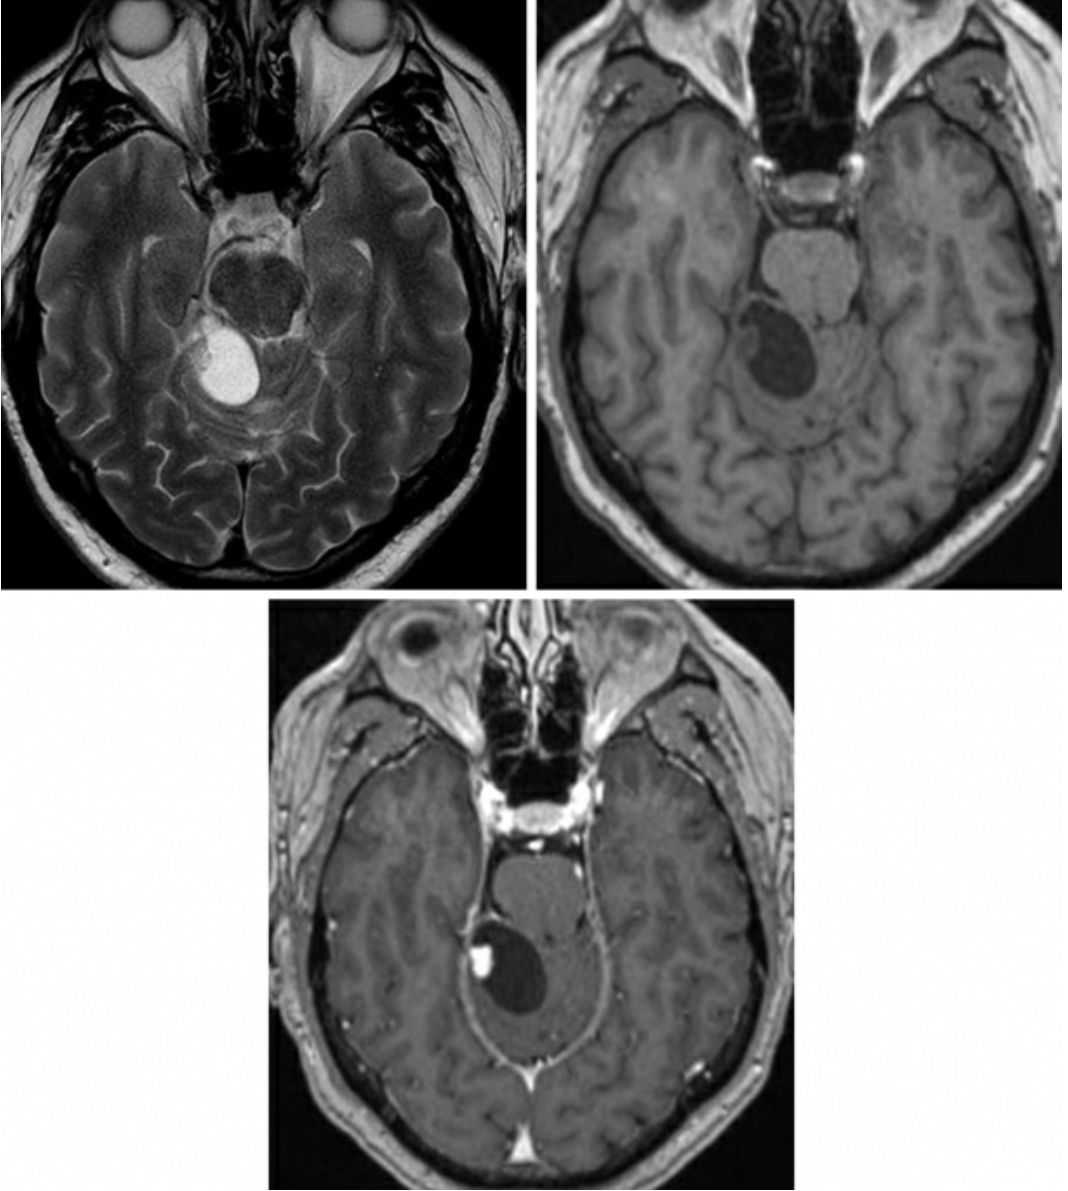

图2:轴位T1增强加权相(第一排左),轴位T2FS(第一排右)示左侧小脑半球后部和右侧小脑半球前部囊实性病变,实性结节强化,符合血管母细胞瘤的表现。矢状位T1增强加权相(中排左)和矢状位T2加权相示脊髓背侧软膜下强化结节,并中央管扩张,符合脊髓血管母细胞瘤的表现。该患者起始表现无痛性血尿,腹部增强CT示(底)肾脏病变不均一性强化,符合VHL综合征患者肾细胞癌的表现。肾脏低密度病变符合肾囊肿表现,也是VHL综合征的特征。

家族性病例常与Hippel-Lindau病(VHL)相关

超过40%的血管母细胞瘤发生于VHL患者

常多发,包括视网膜血管母细胞瘤

VHL患者可发生幕上、视网膜血管母细胞瘤